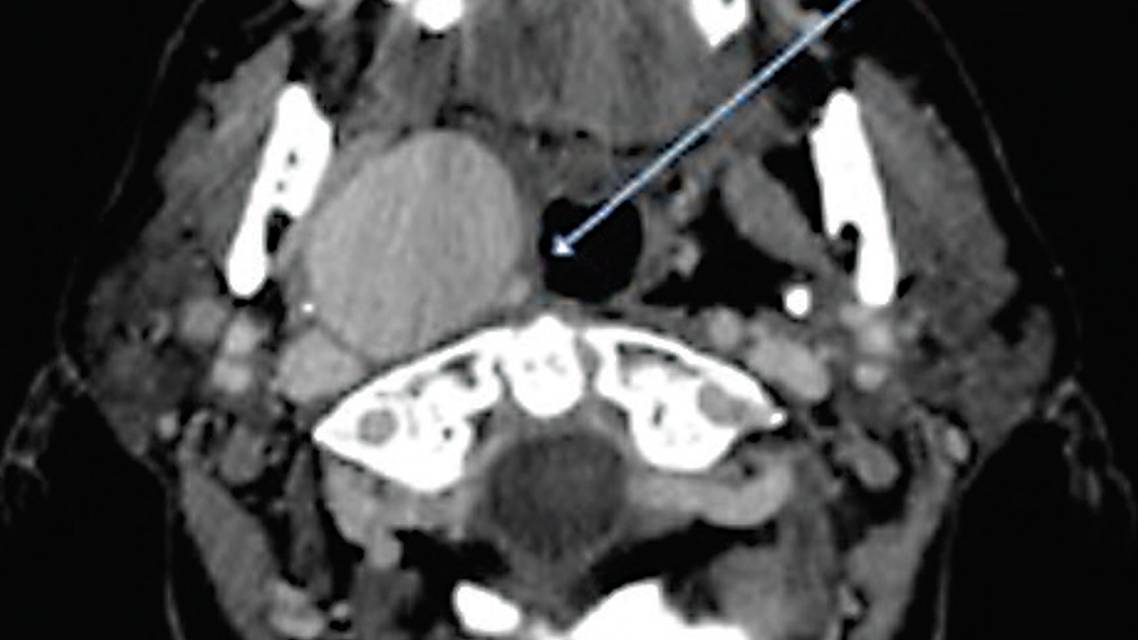

Carotid duplex imaging and a brain CT without contrast incidentally revealed a mass lesion over the right carotid space. Further characterization with contrast-enhanced cervical CT demonstrated a giant aneurysm arising from the proximal right internal carotid artery (ICA) just past its origin (Figure 1). Arising from the aneurysm superiorly and medially was the continuation of the upper cervical right ICA, which was thinned in caliber due to compression by the aneurysm within the carotid space. There were no other aneurysms observed elsewhere in the neck or brain.